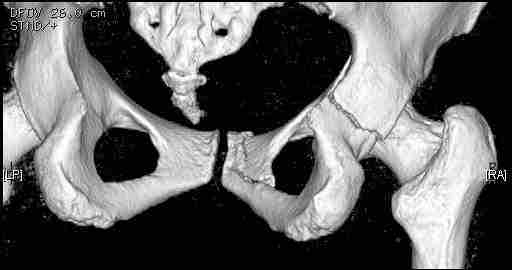

Следом 3d

|